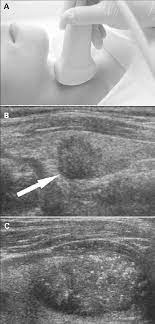

The person operating the ultrasound will sweep, or fan, the probe back and forth to look at different areas in 90 degree angle images. In addition, the following tests may be used to diagnose head and neck cancer: Cancerous lymph nodes can occur anywhere on the neck and are typically described as firm, painless, and sometimes may be immovable. In the normal neck, about 90% of nodes with a maximum transverse diameter greater than 5 mm will demonstrate an echogenic hilus on high resolution ultrasound. Symptoms of head and neck cancer can include:

Air and bone also reflect sound waves. A lump in the neck —cancers that begin in the head or neck usually spread to lymph nodes in the neck before they spread elsewhere. A neck ultrasound may help diagnose (find): Breast ultrasound images are seen from superficial (skin) to deep (chest wall muscle) over a segment of tissue. A neck ultrasound can be used to observe the thyroid gland to look for nodules, growths, or tumors. But now i am worried that the reason the lump didn't show on the ultrasound is because it is actually under the skin in my neck (i.e in my throat) rather than on my actual thyroid/neck. David dang answered 14 years experience radiology node, cyst or others: A small lump on the neck usually is a lymph node, a small sebaceous cyst or a lipoma, although it could be something else. The most common symptom of thyroid cancer is a hard lump on the neck—but most patients experience no symptoms at all. This means that they are larger than about 1 centimeter (about 1/2 inch) across. Optimal positioning and exposure of the neck for ultrasound of the thyroid and parathyroid glands (a, b) and lateral neck for lymph node examination and mapping (c).while the vast majority of patients are supine on the exam table with a pillow supporting the shoulders to allow gentle neck extension, keep in mind that some patients have beautiful anatomy (d) that allows ultrasound exam even in. 1), and the presence of an echogenic hilus within lymph nodes was previously considered a sign of benignity. What does a healthy kidney look like on an ultrasound?

A small device called a transducer is moved over the area. Optimal positioning and exposure of the neck for ultrasound of the thyroid and parathyroid glands (a, b) and lateral neck for lymph node examination and mapping (c).while the vast majority of patients are supine on the exam table with a pillow supporting the shoulders to allow gentle neck extension, keep in mind that some patients have beautiful anatomy (d) that allows ultrasound exam even in. The camera remains attached either to a flexible tube called endoscope or to a probe, while it passes within an opening in your body, often your mouth. In the normal neck, about 90% of nodes with a maximum transverse diameter greater than 5 mm will demonstrate an echogenic hilus on high resolution ultrasound. Ultrasound an ultrasound is sometimes used, especially to look at the thyroid, salivary glands and lymph glands in the neck. A neck lump or nodule is the most common symptom of thyroid cancer. Should your doctor suggest that you undergo a neck ultrasound, you can be confident that your scan will be conducted by highly trained, experienced and caring sonographers. But now i am worried that the reason the lump didn't show on the ultrasound is because it is actually under the skin in my neck (i.e in my throat) rather than on my actual thyroid/neck.

If a biopsy is needed, doctors use ultrasound to scan the area again, ensuring that they know exactly where to place the needle. In addition, the following tests may be used to diagnose head and neck cancer: And my neck look like an old shapai. A lump will form when a cancer cell infiltrates the capsule and multiplies. These are frequently seen in nodules containing papillary thyroid cancer. But ultrasound is usually the first choice for looking at the thyroid and neck structures. The normal neck contains scores of lymph nodes some of which are easily seen with ultrasound. Ultrasound an ultrasound is sometimes used, especially to look at the thyroid, salivary glands and lymph glands in the neck.